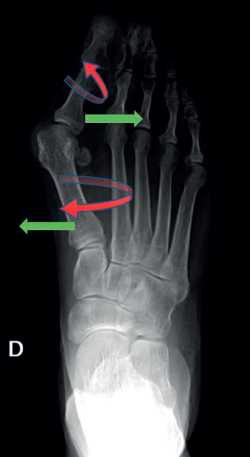

Consiste en una alteración de la articulación metatarsofalángica (MTF) del primer radio del pie. Es una deformidad compleja que incluye, por un lado, la desviación del primer dedo del pie (hallux o dedo gordo) hacia el resto del pie, alejándolo de la línea media del cuerpo (abducto), con una rotación en el plano frontal (pronación del primer dedo). Por otro lado, también incluye la desviación del primer metatarsiano (M1), aproximándolo a la línea media del cuerpo (varo de M1), con una pequeña rotación externa, como se puede ver en la Figura 1. Esta modificación de la articulación afecta a todas las estructuras anatómicas próximas, como la cápsula articular, los ligamentos colaterales, los huesos sesamoideos, la musculatura intrínseca y la extrínseca)(2).

Figura 3. Ejemplos de hallux valgus intervenidos en nuestro centro: A: pie izquierdo pre-intervención quirúrgica (IQ); B: pie izquierdo post-IQ; C: pie derecho pre-IQ; D: pie derecho post-IQ.